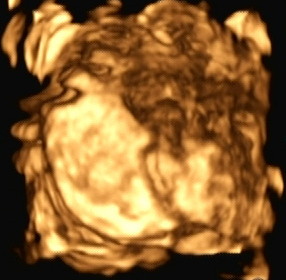

Ein zunächst durchgeführtes CTG war unauffällig. Im Rahmen der sonografischen Untersuchung zeigte sich der Fötus soweit beurteilbar zeitgerecht entwickelt. Dennoch konnte ein Anhydramnion festgestellt werden(Abb. 1, 2), weshalb auch kein fetales Gesicht darstellbar war (Abb. 3).